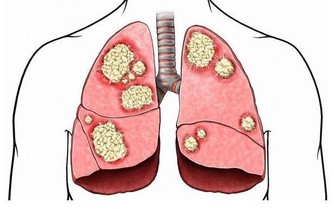

根據衛福部公布的民國103年十大死因,癌症連續33年蟬聯榜首,

占約所有死亡人數3成,平均每11分24秒就有一人死於癌症。

卻有抗酸化、抑制癌細胞增殖、致癌物質無毒化、強化免疫力等功效,

免於身體受到體內毒素的侵害,除了能防癌外,